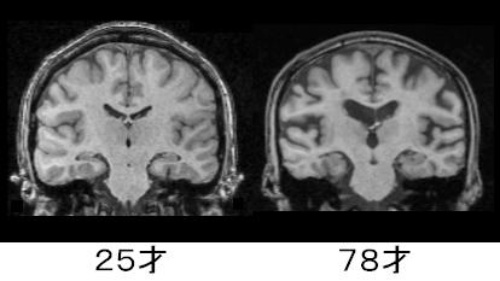

こども期の脳のはたらき 日宇歯科 矯正歯科

ネット ゲーム依存と脳 ネット依存患者の脳 健常者に比べて萎縮している 群馬県前橋の小林大栄 行政書士 土地家屋調査士 測量設計事務所 前橋市南町三丁目 中之条町赤坂 相続 登記